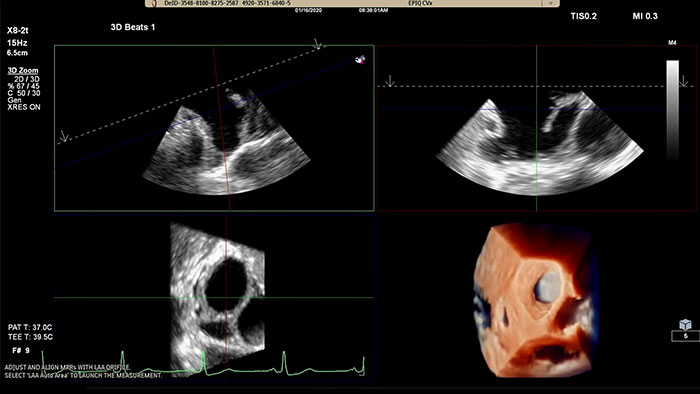

Assessing the left atrial appendage quickly, easily, intuitively.

Rapidly acquire LAA orifice measurements in both traditional rendering or in TrueVue Glass rendering, with 3D Auto LAA